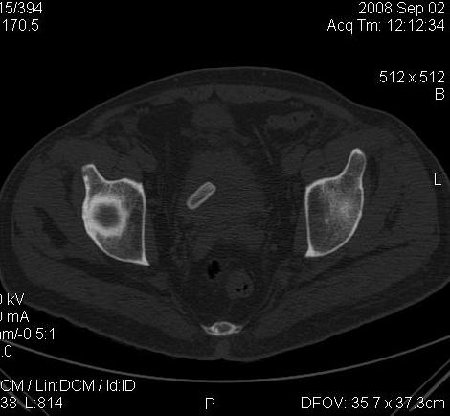

КТ Малого таза.

Что в мочевом пузыре? :?: ;)

Я тоже так думал! Урологи выполнили цистоскопию, оказалось камень, такой причудливой формы.